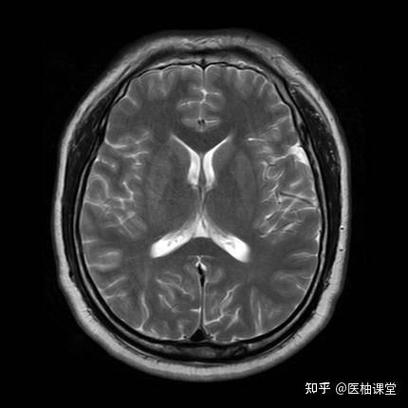

大脑后动脉区域:

(图片来源网络,侵删)- 位置: 枕叶和颞叶的后部。

- 看什么: 观察枕叶(视觉中枢)是否有低密度灶,患者可能会出现视野缺损(偏盲)。